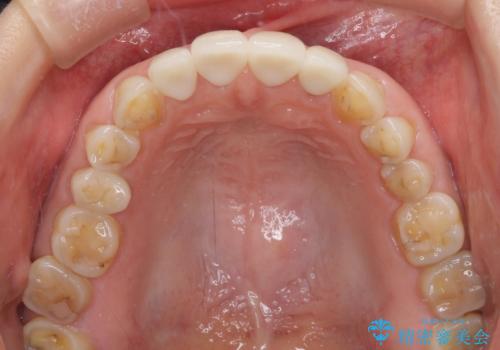

- 咬み合わせと度重なる応急処置の繰り返しにより、前歯がガタガタになってしまったとのことで来院された患者様です。

4本の前歯が気になっていたので、全てをオールセラミッククラウンにて補綴治療を行うこととしました。

4本とも治療前の歯髄の状態は正常でしたが、補綴治療により歯を大きく削ることになるため、歯髄が炎症を起こすリスクがあることを了解いただきました。

口元への目線ばかりを気にしていた状態から、自然な口元へと変貌し、患者様には大変満足していただきました。